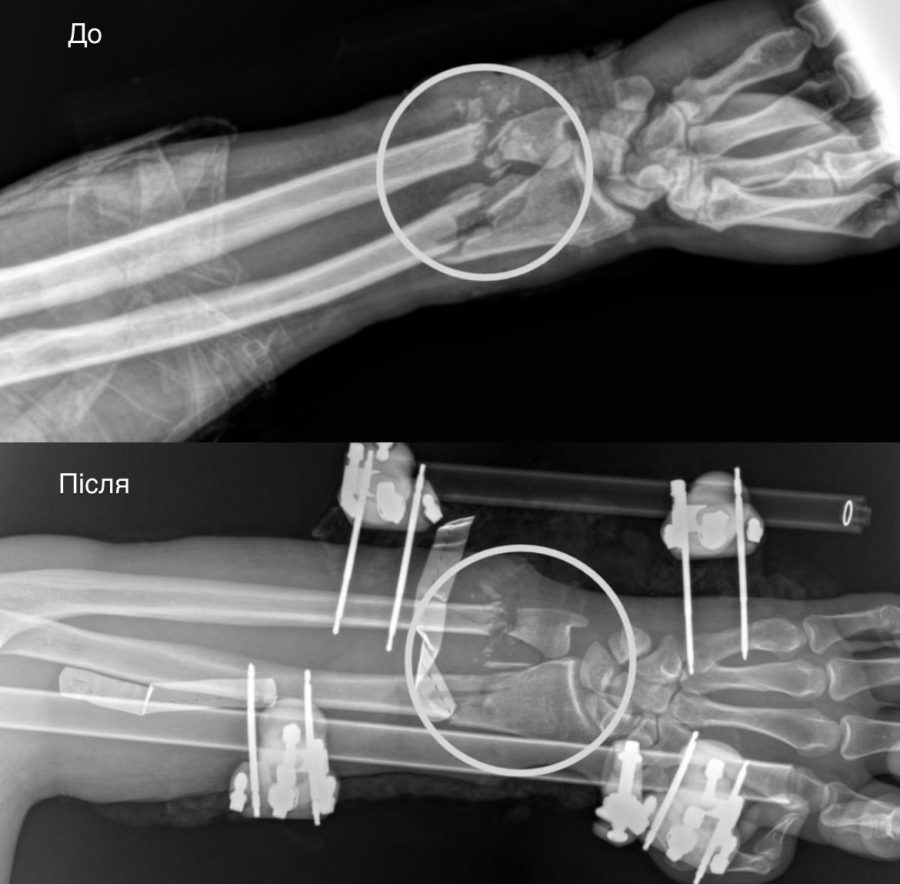

Першими працювали ортопеди-травматологи – вони стабілізували переламані кістки передпліччя за допомогою апарата зовнішньої фіксації. Далі судинні хірурги відновили кровопостачання, що стало вирішальним етапом, адже без циркуляції крові тканини швидко змертвіли б.

Після цього хірурги відновили м’які тканини – ушили пошкоджені сухожилля та м’язи, щоб повернути згинально-розгинальну функцію. Нерви підготували до наступного оперативного втручання, яке заплановане через місяць-два. Завершальним етапом стала аутодермопластика: реконструктивні хірурги закрили дефект власною шкірою пацієнта.